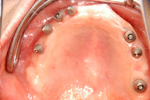

① 60才代の方です。まったく歯がありません。従来の総入れ歯を使用されていました。

食事でかむたびに入れ歯が動き、長い間不自由さを感じていました。上あごは長い間の入れ歯だった為、骨の厚みがなくなってインプラントは不可能でした。下あごの骨の厚みは可能な状態でした。

② 下あごにインプラント(人工歯根)を埋入しました。これで、まったく歯がなかったところに歯の土台が固定されました。

ここに、人工の歯を乗せしっかりと固定します。従来の入れ歯は歯がまったくない場合、歯肉に乗せるしかありませんでした。

③ 下あごの人工歯です。インプラントの上にキャップを入れてあります。

④ 従来の入れ歯のように見えますが、大きな違いは中央の黒く見える部分(実際は銀色)を上図の埋入したインプラント (人工歯根)に乗せしっかりと固定します。これが動かない理由です。

⑤ インプラントの上に取り外し式の入れ歯が入りました。

⑥ インプラントが土台の下の総入れ歯が入りました。

60才代 女性 5本埋入

総額:225万円(税別)

治療期間:6ヵ月

リスク副作用:一時的な食事制限によるQOLの低下。腫脹。神経障害。出血。咬合歯の負担増加。